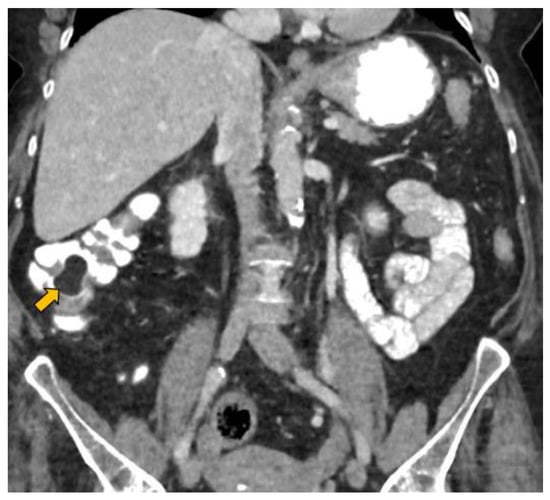

- Lesion location: The segment of the colon in which the lesion is located is an important factor if HS is to be used in follow-up. The rectum is a non-assessable segment. The position of the sigma in the pelvis, the disposition of the transverse colon [20] or the existence of dolichomegalosigma [15,20] are factors that limit the study of these colonic segments. However, the cecum, and ascending and descending colon are more superficial segments and are easier to assess by HS. Our lesion located in the cecum is accessible by HS. However, studying the cecum has peculiarities. First, the presence of faecal remains. Faecal remains frequently accumulate in the right colon [14,15,20]. Faecal remains are observed in the lumen of the colon during retrograde instillation of saline solution and can be moved by using the transducer to compress the abdomen rapidly and lightly [10,11,14,20]. Moving the patient sideways also allows the faecal matter to be displaced, allowing better visualisation. However, they can sometimes be abundant. The concentration of faecal matter can be reduced by increasing the infusion of saline solution [14] if the patient can tolerate it. It is also possible to decrease the faecal concentration by emptying and refilling the colon [20]. Thus, the saline solution together with the faecal remains return to the bag and a new bag of saline solution is used. Second, the ileocecal valve can also be mistaken for a lipoma. The ileocecal valve is seen as a pseudopolyp image projecting into the colon lumen from the ileocecal junction [38] (Figure 4). A lipoma in the cecum may be confused with lipomatosis of the ileocecal valve, which is a more common entity than lipoma [7,36].

Figure 4. The ileocecal valve (yellow arrow) is observed as a pseudopolyp hyperechoic image projecting into the colon lumen from the ileocecal junction.